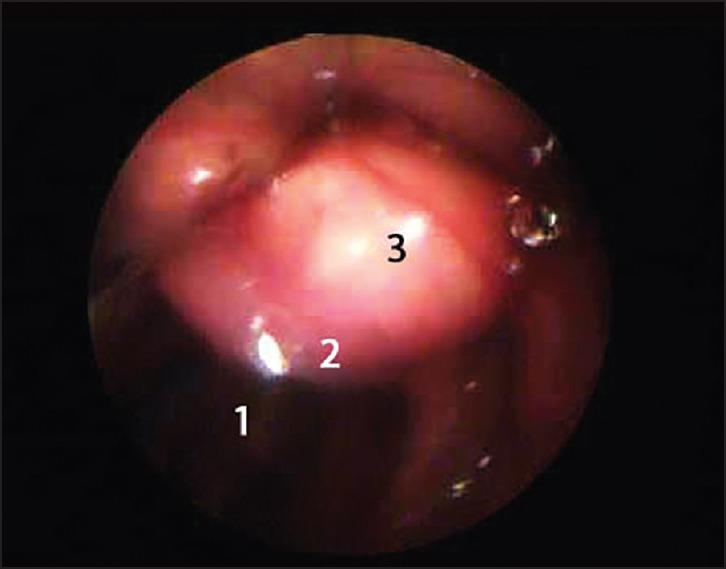

Unrecognized epiglottic cyst: Cause of difficult mask ventilation.